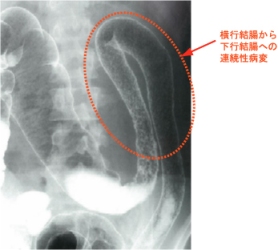

<注腸X線検査>

ハウストラの消失(鉛管像)や腸管の狭小・短縮が連続性に認められます。

しかし、検査を行うには下剤の投与等が必要でそれにより病状悪化がみられるため最近では行わなくなっている

ようです。